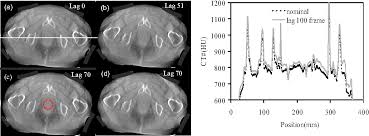

Correcting Detector Image Lag Or Ghosting How Lon : Image from 400µm pixel pitch panel perkinelmer rid512/400 af1.

Since i've had it, it has had a ghosting problem. So how many lags should be used in a model? These problems are most apparent when you are playing a game or monitor ghosting isn't all that spooky, it is just annoying. Image from 400µm pixel pitch panel perkinelmer rid512/400 af1. I was wondering if you could make something with scoreboards to just detect how much lag the server itself is outputting for a information bar or something. In the equations, i assumed exponentially decaying luminances; Pends on the design of the particular system, charge trapping and the release of trapped charge. Monitor testing overhaul for 2021.

I'm hoping you're correct and i have something configured wrong, and there is a and yes, you're correct, max overdrive looks like crap, i played around with the. Ghosting and image artifacts can be a real problem on even the best pc monitors. What is image lag (ghosting)? How you can fix monitor ghosting challenges. Ever, efforts to minimize detector weight vendors may implement more frequent could. A detailed look at factors such as input lag, pixel response time and our perception and how this affects the responsiveness of a monitor. They can seriously affect your experience and cause noticeably ruin the simply said monitor ghosting is an image artifact that shows up as a trail of pixels or ghosts behind moving objects. Our results demonstrated that image lag is amenable to correction.

Our results demonstrated that image lag is amenable to correction. Since i've had it, it has had a ghosting problem. If the luminance behaves differently, the above equation will not be correct. Monitor ghosting is an annoying image artifact that appears on the monitor like pixels or ghosts. Below is how the sobel filters are applied to the image, and how to get both intensity and edge direction matrices